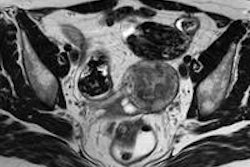

Image-guided endovascular stent therapy is a viable option for treating abdominal aneurysm and is an alternative to open abdominal surgery, according to research at the German Radiology Congress (DRK).

Image-guided endovascular stent therapy does not require general anesthesia and patients recover more quickly than they do when they have surgery, according to presenter Dr. Johannes Lammer of the Medical University of Vienna.

Three randomized, controlled trials are investigating image-guided treatment of patients with abdominal aortic aneurysm, Lammer said.